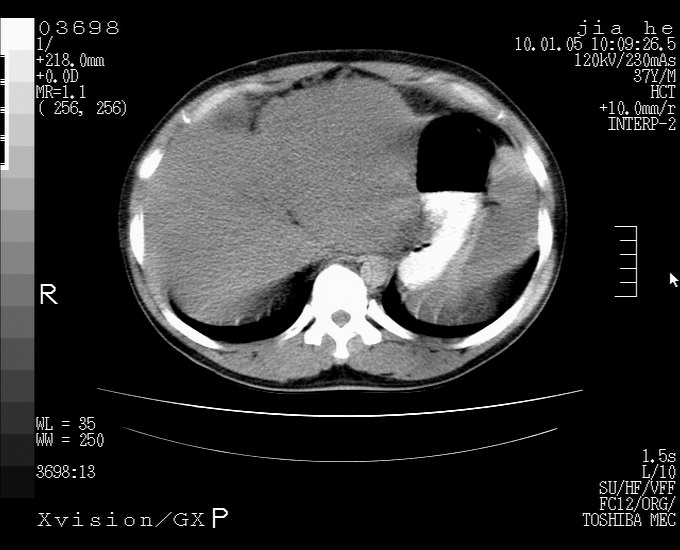

标题: CT23988:男,40岁,B超提示腹部肿物,请各位老师给看看。 [打印本页]

标题: CT23988:男,40岁,B超提示腹部肿物,请各位老师给看看。

左叶够大的,且与胰腺欠清晰,请增强扫描

肝左叶增大,建议增强扫描。

1.该患者有腹部手术史

2.脾大,肠系膜密度增高,有多发索条影,胰腺边缘毛糙,腹膜增厚,推测有肝硬化,门脉高压,腹膜炎和/或胰腺炎

3.肝左叶巨大站位,并腹腔淋巴结肿大,肝癌或肝间叶来源恶性肿瘤,也不排除大网膜间质瘤侵及肝左叶

建议:增强或磁共振

还有个异位胆囊。临床资料太少,肿瘤、左叶发育异常、肝硬化。不过看密度是个低密度为主的,新生物倾向于第一位。强化吧!

考虑肝左叶外侧段癌并腹膜后淋巴结转移.建议增强进一步检查.